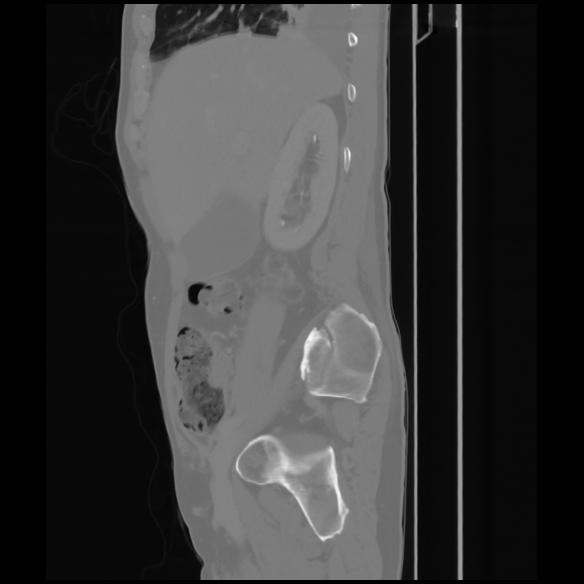

7 CUERPO,CE,Sagittal,3.000,CUERPO,Sagittal,